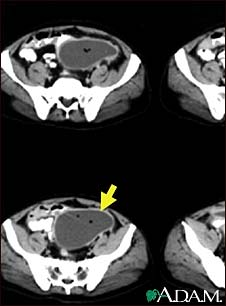

Intra-abdominal abscess, CT scan

CT scan of the pelvis showing a large intra-abdominal mass.